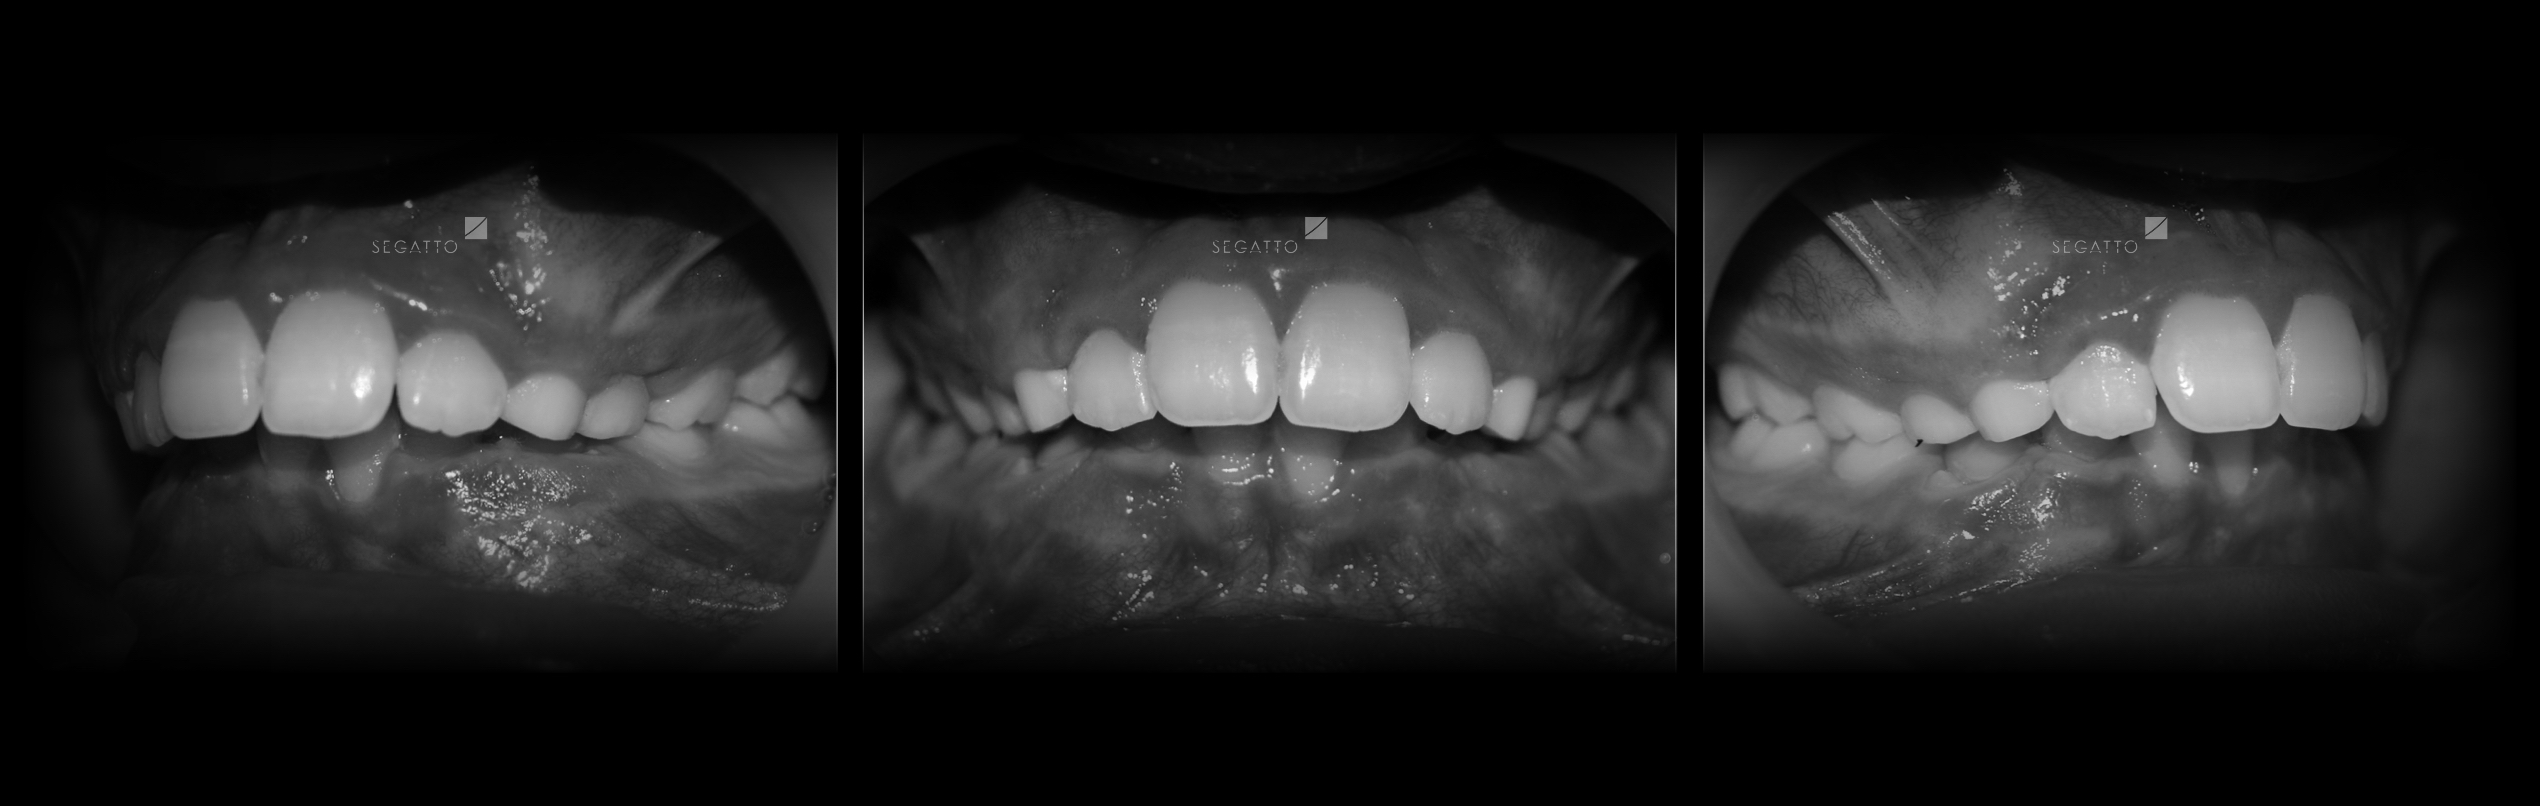

Orthodontics

Cases